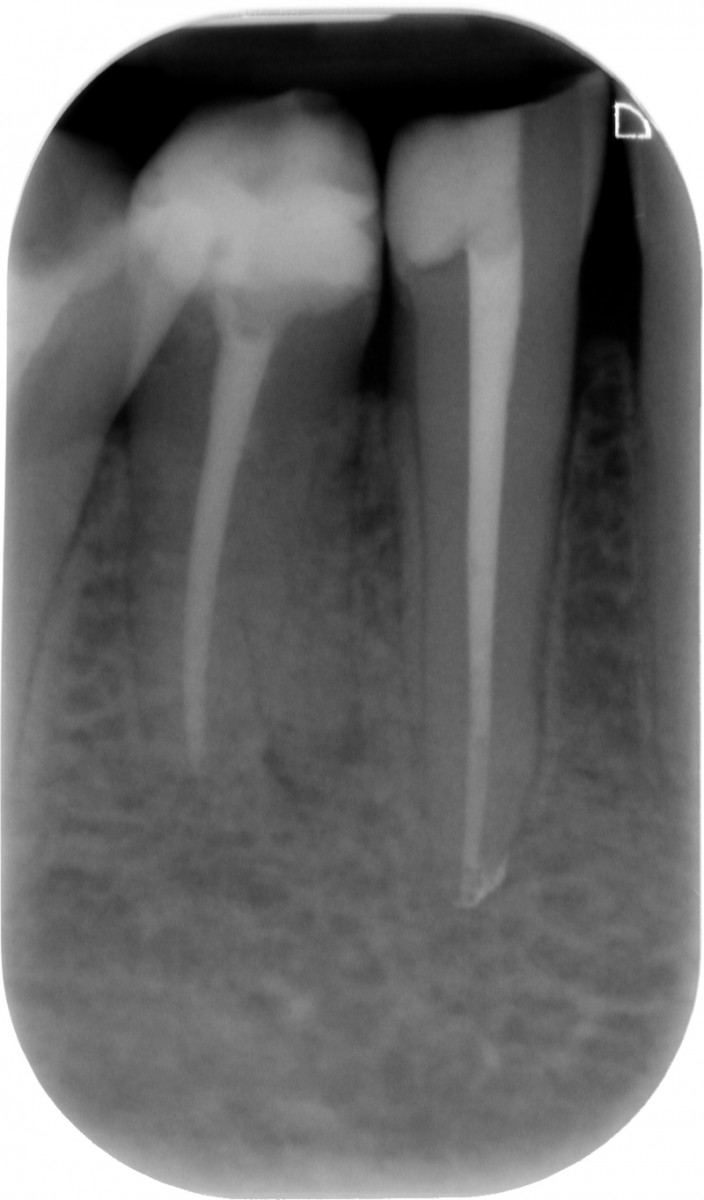

The gutta-percha point inserted into the root canal properly, adapting it to a size almost equal to the one employed to shape the apical terminus. Not wider, not smaller. Here are exposed a couple of cases made by shaping the root canal with a NiTi instrumentation technique and followed up for 9 to 12 months (Fig. 1-6).

It’s encouraging its easy handling and quite precise adaptation to the apical part of the root canal. The periapical healing, assessed by 2D-Rx, is considered satisfactory but further analysis and clinical studies related to these particular cements should be performed to confirm the first encouraging results.